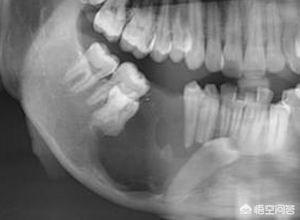

4. 顎の嚢胞性腫瘍などの病変。歯を包む顎骨に嚢胞や腫瘍などの病変があり、顎骨の骨質が著しく変化している場合、病変部位の歯は緩みます。

治療法:顎病変の外科的治療、病巣部の抜歯、歯根端手術。